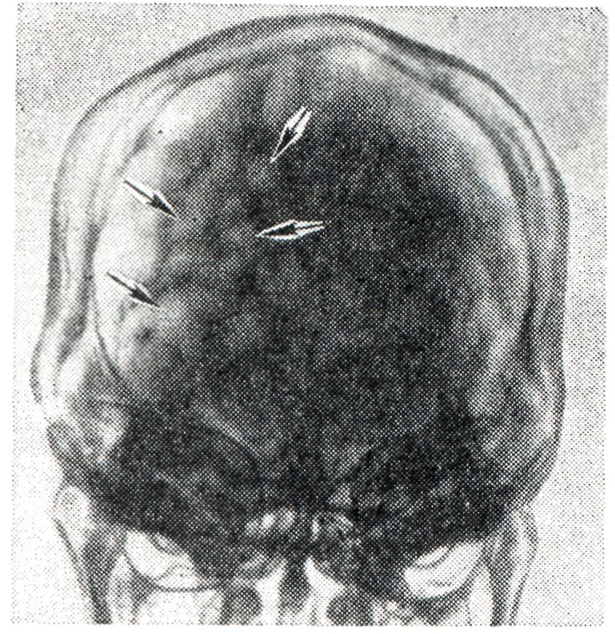

Башенный череп. Изменение формы черепа, признаки краниосклероза и усиление пальцевых вдавлений — указаны стрелками (рентгенограмма).

Иногда наблюдаются эпилептические припадки. Отмечены нарушения психики, в редких случаях — слабоумие. Могут быть патологические рефлексы, атаксия, эндокринно-обменные и вегетативные нарушения. Сочетание Б.ч. с прогнатизмом, экзофтальмом, нистагмом, умственной отсталостью, эпилептоидными приступами, атрофией зрительного нерва описывается как синдром Терсиля. Могут быть стационарные (компенсированные) и прогредиентные формы Б. ч. На краниограмме отмечается отсутствие черепных швов в сочетании с Б. ч., наличие выраженных пальцевых вдавлений (рис.), укорочение и западение передней и средней черепных ямок, булавовидная спинка турецкого седла.